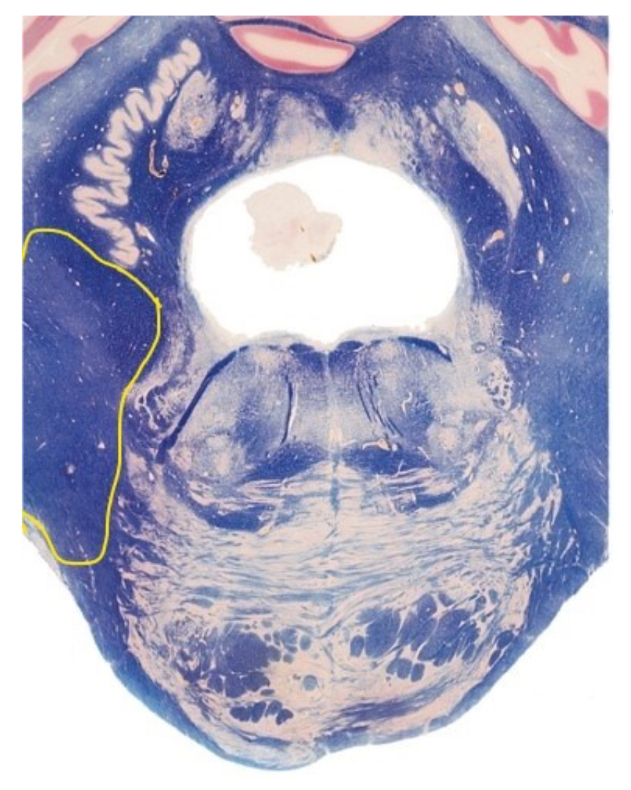

8

The section is through the ________________?

A

caudal pons

9

The yellow line represents?

axons of CN VII

10

The yellow lines represent?

pyramidal decussation